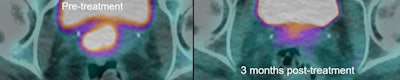

40-year-old LACC patient with stage B disease, node negative. Indeterminate residual T2-weighted signal change post CRT -- grade 3 (moderate response). Indeterminate residual T2-weighted signal change post CRT -- grade 3. No corresponding residual metabolic activity on PET/CT -- grade 1 (complete metabolic response). Patient remains disease-free three years later.

Indeterminate residual T2-weighted signal change post CRT -- grade 3. No corresponding residual metabolic activity on PET/CT -- grade 1 (complete metabolic response). Patient remains disease-free three years later."Our current work is focused on evaluating whether extracting novel (quantitative) features -- including metabolic tumour volume and standardized uptake value metrics derived from FDG-PET/CT as well as radiomic features along with quantitative feature analysis of MRI -- has a greater ability to predict patient outcome when compared to qualitative analysis," he told AuntMinnieEurope.com.